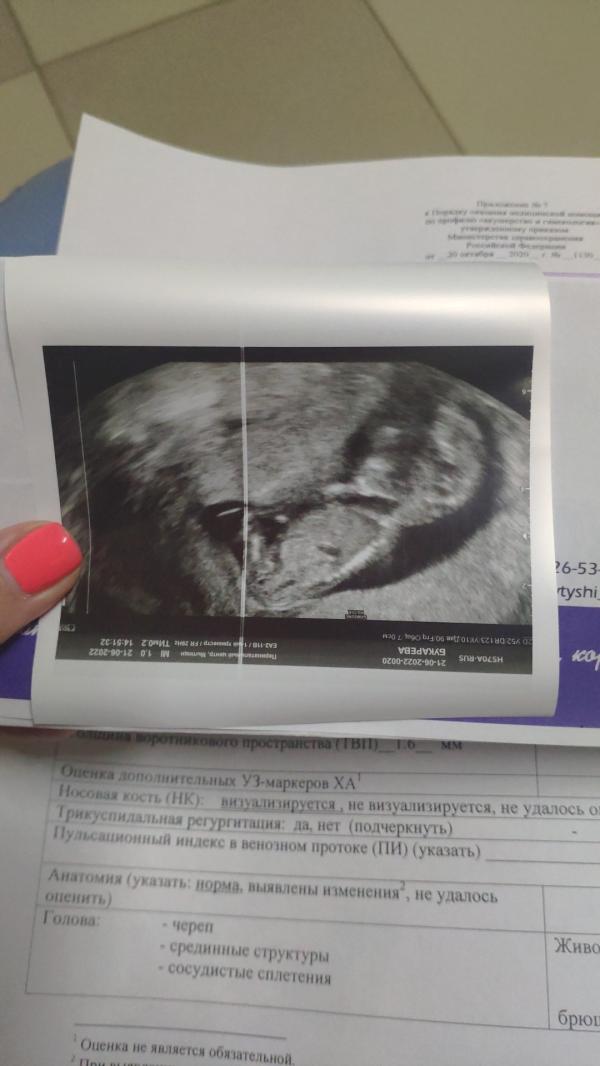

1-й скрининг сходила сегодня.. все в порядке малыш 😍 а так мне сразу сказали что тебе сказать пол? Я сказала что нет, на бумажке 😊 а нет проблем, и все.. 😊 в июле сюрприз 💜 узнаем малыша кто) и сасое главное здоровый малыш, и меня больше радует 🔥🤰